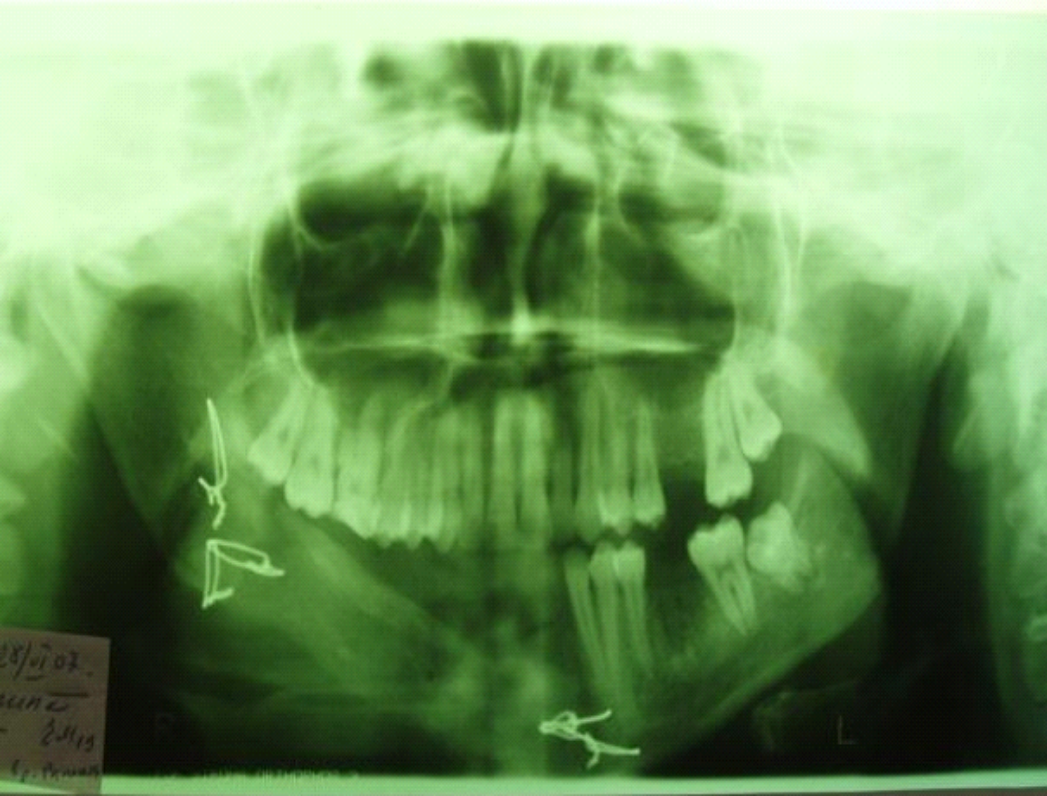

When collecting the patient's life history, it was found that in 2016 there was a second pregnancy, which ended in childbirth. In the summer of 2023, the patient noticed a change in the shape of the alveolar part in the area of tooth 3.7, but did not seek medical help. CBCT was performed –

a focus of bone rarefaction was found, heterogeneous in density in the projection of tooth 3.7, up to 1.5 cm (Fig. 8). Bulging of the cortical plate on the lingual side. here are no signs of relapse of the neoplasm in the upper jaw and in the area of implant fixation on the lower jaw. Osteointegration is observed at the border of the bone-implant unit. A preliminary diagnosis is chronic periodontitis of tooth 3.7, neoplasm in the area of the alveolar process of the lower jaw on the left.

Fig. 8. OPTG: neoplasm in the lower jaw area on the left, 2023

Patient M. underwent extraction of tooth 3.7, scraping of the neoplasm was performed, the material was sent for cytological examination. Given the clinical picture of the polyostotic form of osteoclastoma, in terms of differential diagnostics, it was recommended to conduct an X-ray examination of all bone structures in order to exclude myeloma disease. After receiving the research results, myeloma disease was not confirmed.

As a result of X-ray, cytological examination and subsequent pathohistological examination, the diagnosis was established: fibroma of the lower jaw on the left, the presence of relapse of osteoblastoclastoma was not confirmed. In April 2024, the fibroma of the lower jaw on the left was removed at the Clinical Hospital of Perm State Medical University using intraoral access. At the time of discharge, the patient's condition was satisfactory, orthopedic treatment and further dispensary observation were recommended for the patient.